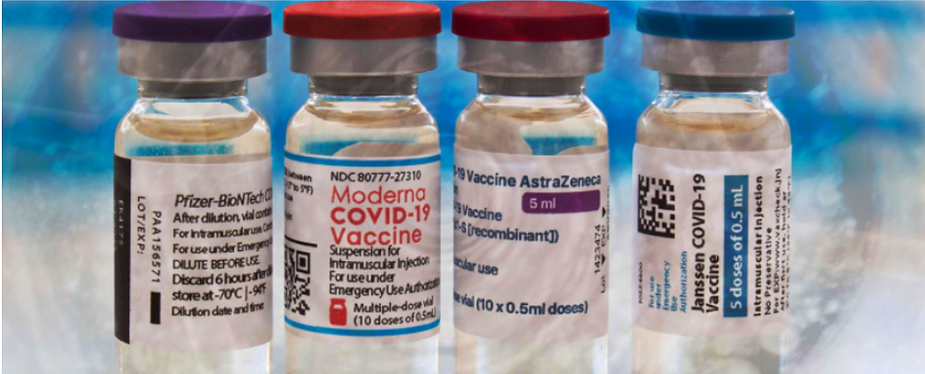

Abstract: Currently there are four major pharmaceutical companies who manufacture a SARS-CoV-2 now called SARS-CoV-19 vaccine. These manufactures and their vaccine are Pfizer–BioNTech mRNA Vaccine, the Moderna-Lonza mRNA-1273 Vaccine, the Serum Institute Oxford Astrazeneca Vaccine and the Janssen COVID -19 Vaccine, manufactured by Janssen Biotech Inc., a Janssen Pharmaceutical Company of Johnson & Johnson, a recombinant, replication-incompetent adenovirus type 26 expressing the SARS-CoV-2 spike protein.